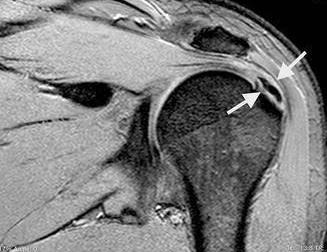

การรักษาเริ่มแรก แพทย์จะทำการวินิจฉัยโรคจากอาการ การซักประวัติและตรวจร่างกาย ร่วมกับการตรวจแบบอื่นเพื่อยืนยันการวินิจฉัย เช่น ตรวจเอกซเรย์เพื่อดูความผิดปกติของกระดูก หรือตรวจ MRI เพื่อวินิจฉัยภาวะเสื่อมหรือการขาดของเส้นเอ็นบริเวณไหล่ และยังสามารถให้รายละเอียดของกระดูกอ่อนและเนื้อเยื่อรอบข้อไหล่ได้ดี